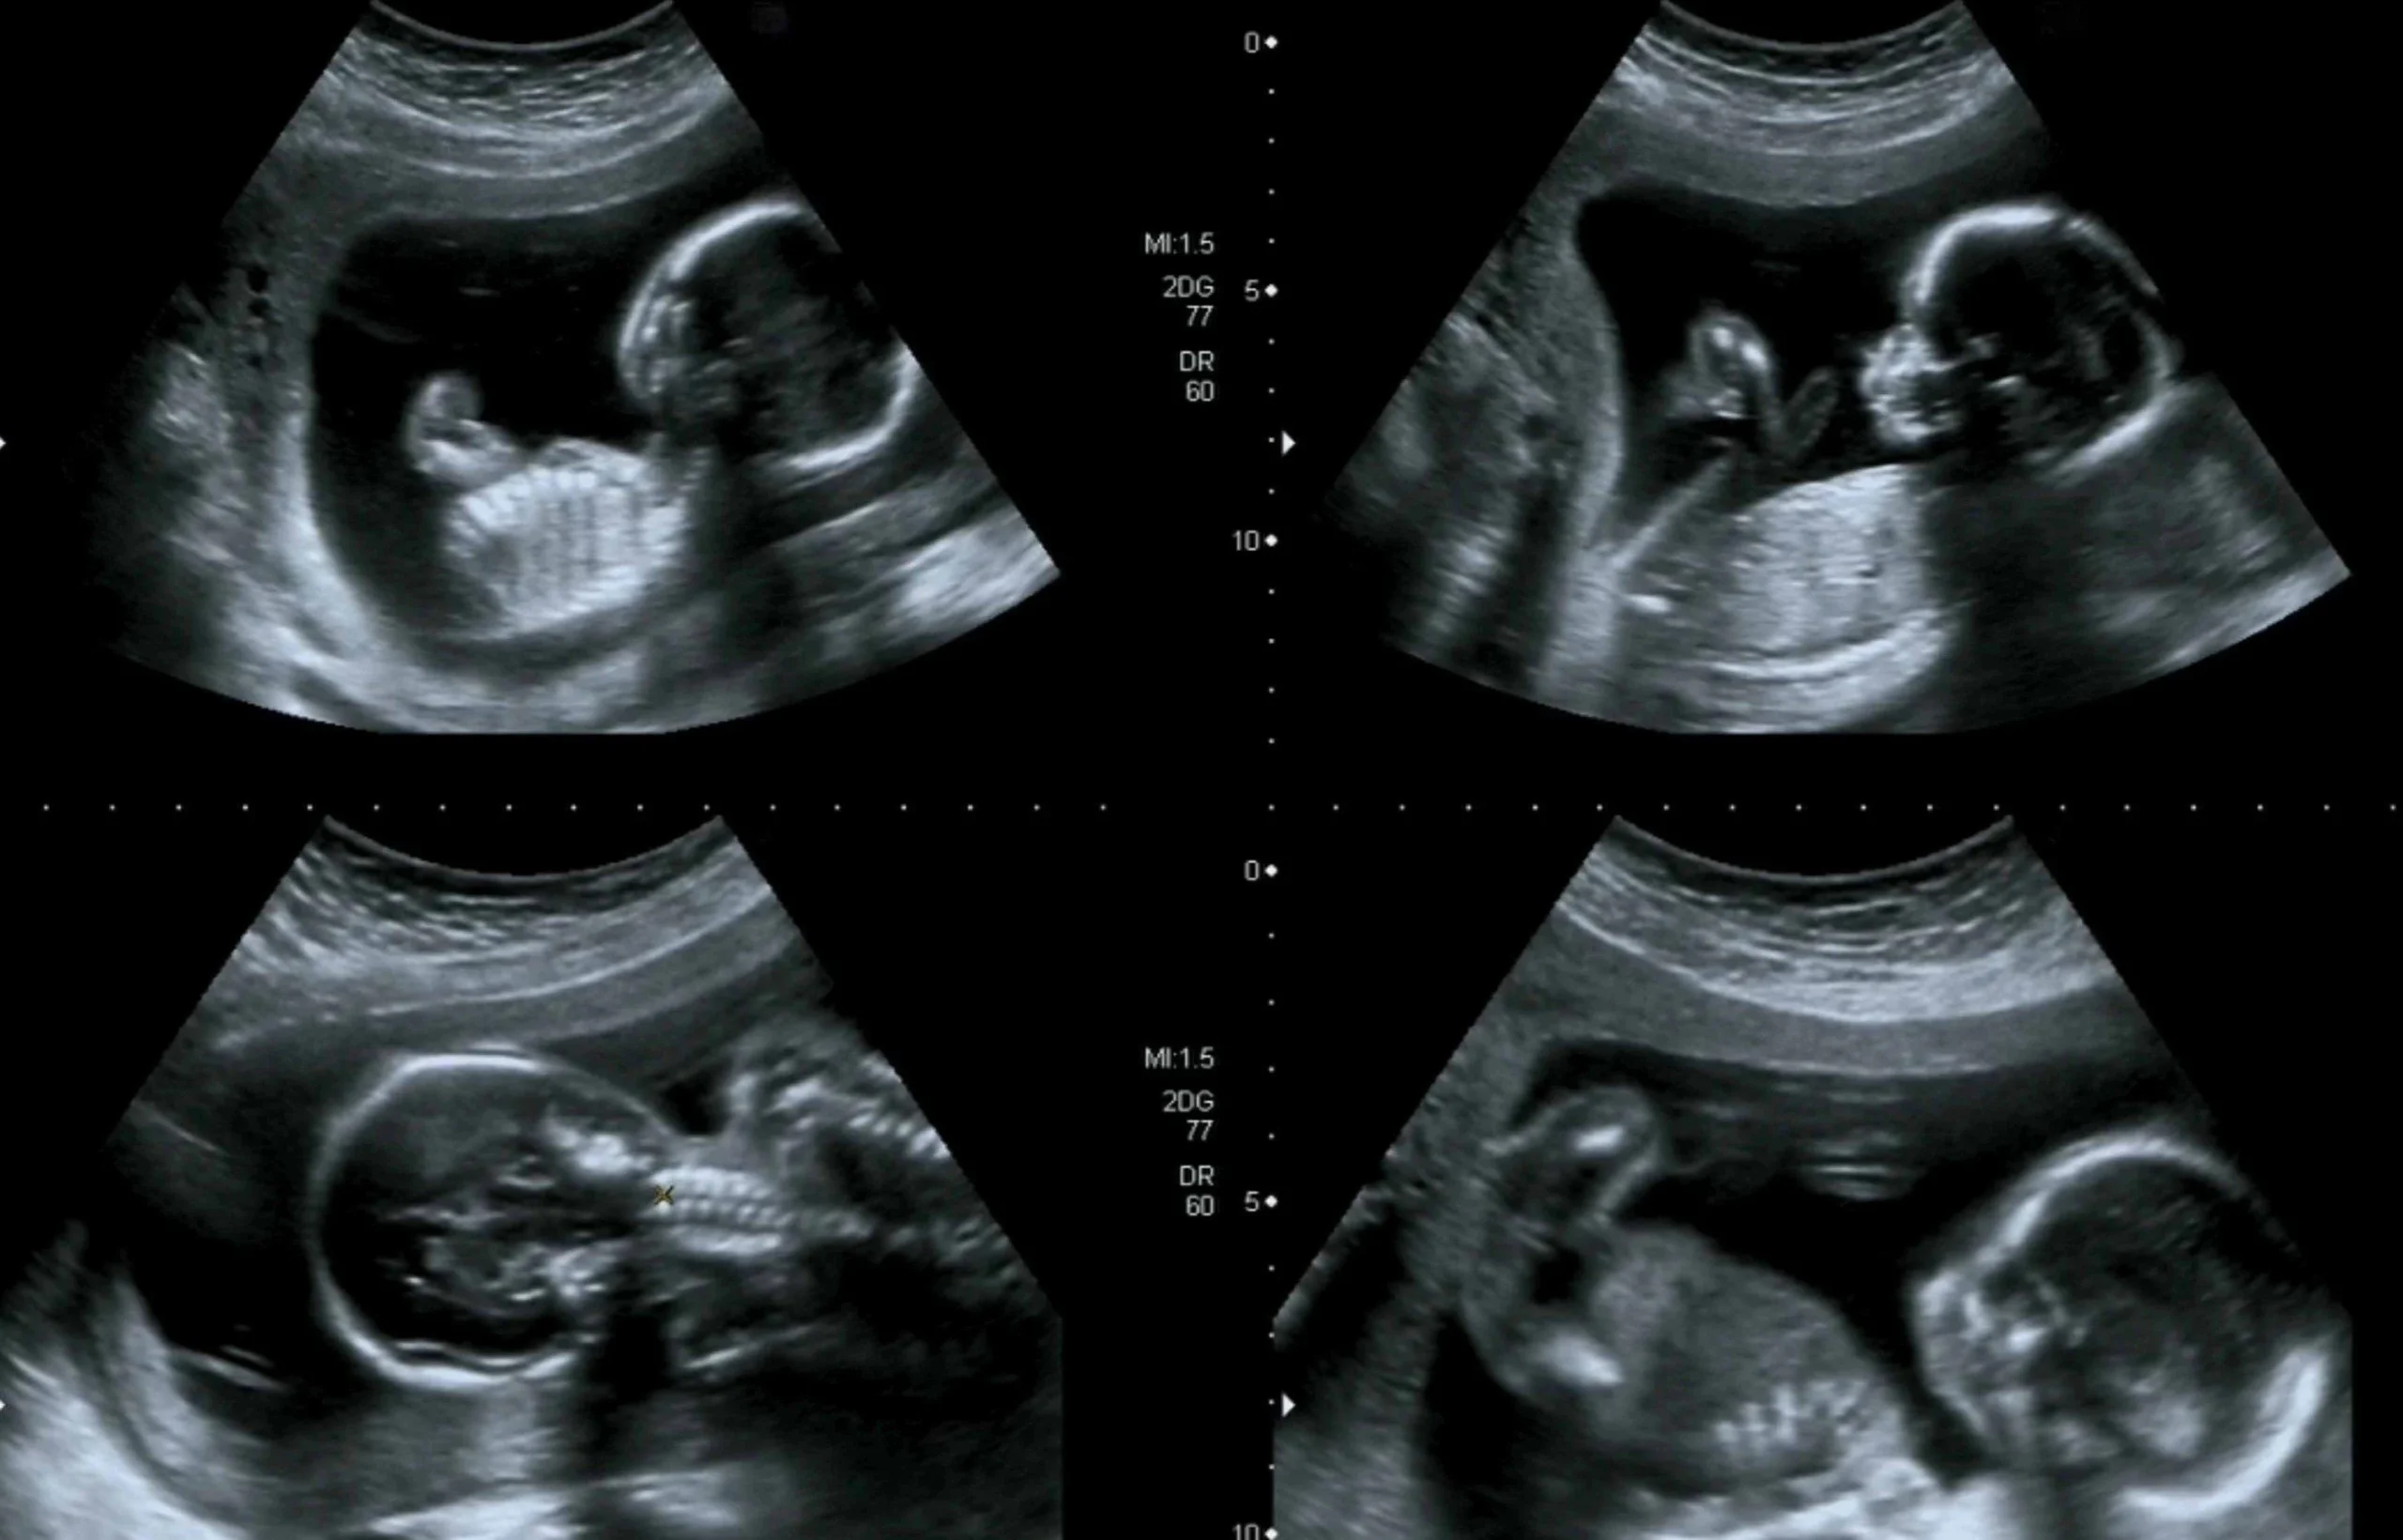

Die Frage, wann der letzte Ultraschall vor der Geburt stattfindet, ist eine, die viele Schwangere beschäftigt. In Deutschland sind die Vorsorgeuntersuchungen in der Schwangerschaft gesetzlich geregelt und beinhalten in der Regel drei Ultraschalluntersuchungen, eine pro Schwangerschaftsdrittel. Diese Untersuchungen sind für die Schwangere kostenlos.

Im letzten Trimester der Schwangerschaft kann der Ultraschall wichtige Informationen über den Gesundheitszustand des Kindes und die Entwicklung der Schwangerschaft liefern.

Zu den Informationen, die der Ultraschall im letzten Trimester liefern kann, gehören:

- Die Größe und das Gewicht des Kindes

- Die Lage des Kindes im Bauch

- Die Menge des Fruchtwassers

- Die Plazenta-Lage und -Funktion

- Der Nabelschnurfluss

- Die Entwicklung der Organe des Kindes